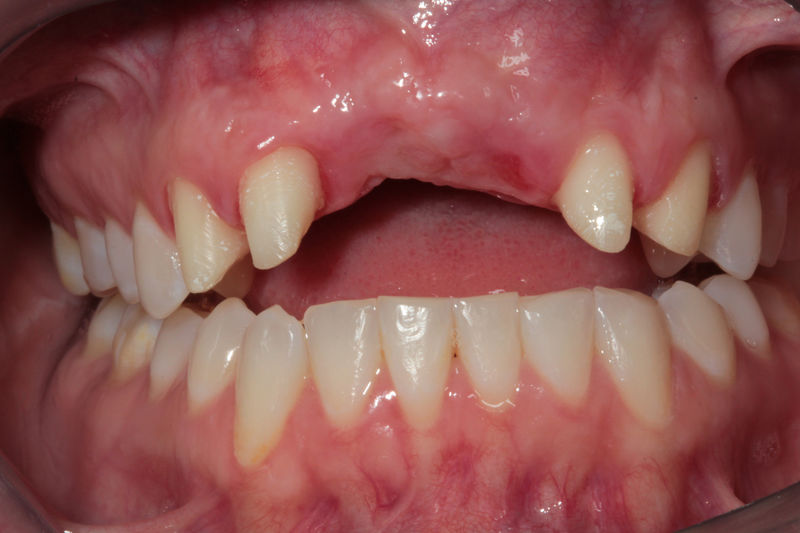

Las prótesis dentales son aparatos o dispositivos que se utilizan para reemplazar los dientes ausentes y las estructuras orales relacionadas.

Restauraciones fabricadas en el laboratorio con materiales estéticos, los cuales se usan para reemplazar dientes ausentes usando coronas como soporte. Para poder enviar el caso al laboratorio se toman impresiones utilizando materiales de impresión o técnicas modernas digitales.

Implante fracasado, extracción, carillas, coronas y prótesis fija.